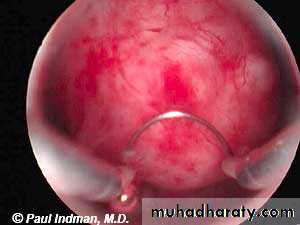

Hysteroscope (diagnostic and therapeutic)

Show polyp + loop diathermy + cauteryIUCD minera

Indication used in contraception // progesterone releasing // used in menorrhagia to reduce the amount of bleeding.Complication infection // ulceration // ectopic pregnancy // undiagnosed bleeding.